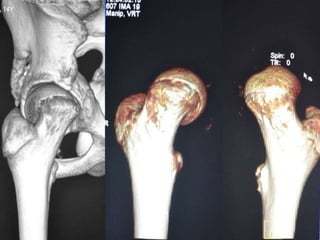

 CT SCAN-

Accurately measures extent of epiphyseal displacement & angulation.